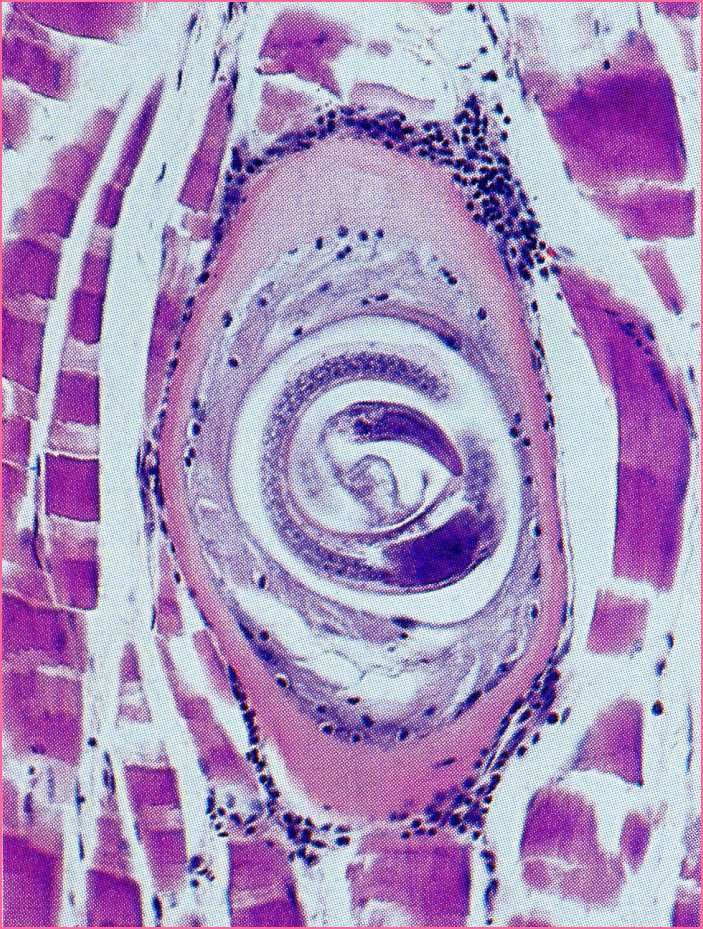

旋毛形线虫